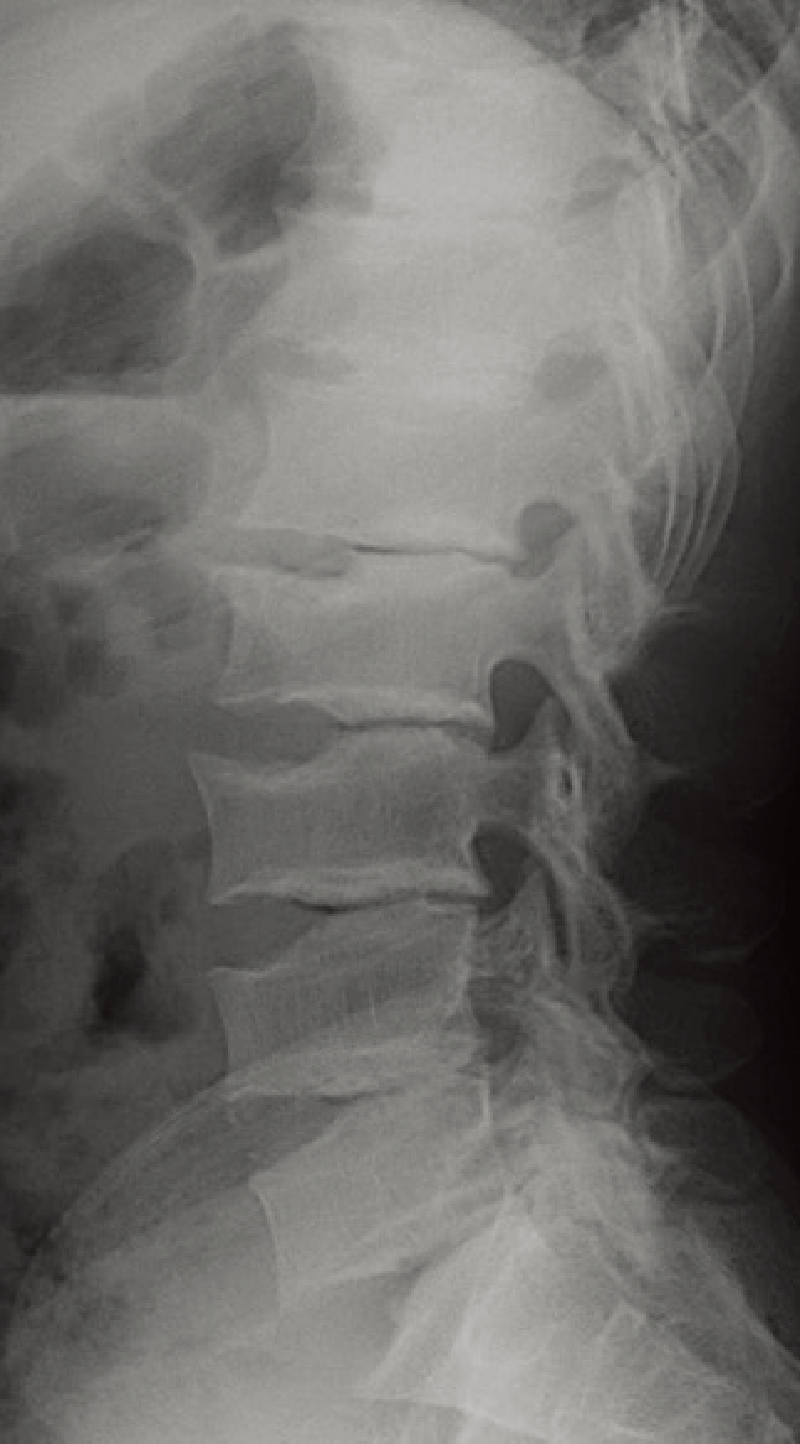

特徴的な画像所見:腰椎の前弯がみられる。扁平椎で椎体の前方舌状突出像(anterior tongue)が特徴的である(A)。

A. 脊椎側面像(2歳5カ月、女):椎体前方の舌状突出を伴った扁平椎が特徴的である。

手指の短管骨は著しく短く、指節骨が弾丸状(bullet shaped)である。長管骨では骨端が小さく、骨幹端は幅が広い(B)。

B. 両下肢正面像(2歳5カ月、女):骨端は小さく、骨幹端は幅が広い。

AとBは同じ症例。

椎体前方の舌状突出はモルキオ症候群に類似する。

四肢短縮型低身長であること、顔貌正常で骨格系以外の合併症が少ないことなどがムコ多糖症とは異なる。